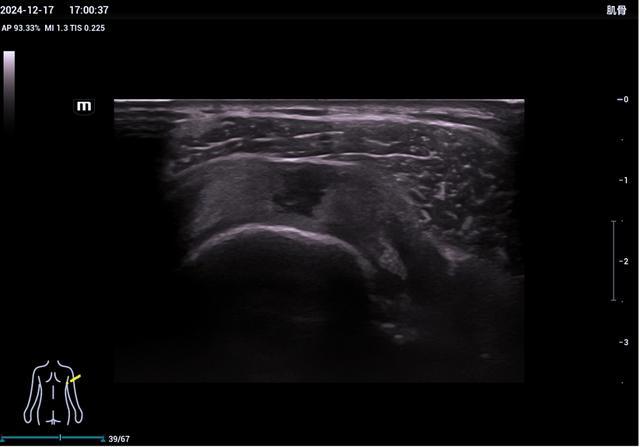

2、肘关节超声检查

肘管综合征、肱骨内上髁炎(高尔夫球肘)、肱骨外上髁炎(网球肘)、尺骨鹰嘴滑囊炎等。

▲肱骨外上髁炎

(网球肘)

▲肘管段尺神经卡压